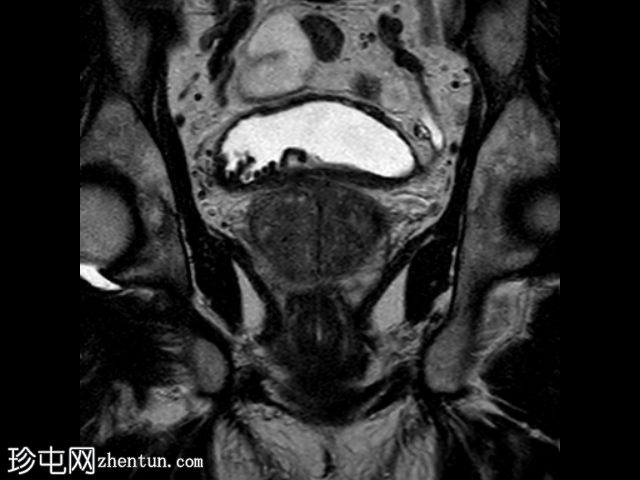

在T1和T2加权像上,于膀胱底部及右下外侧面偶然发现一处呈蛇形缠绕状的低信号区。动态序列中可见快速对比增强,提示所有影像学表现均源于血管,信号缺失与动静脉畸形有关,该畸形至少由膀胱下动脉供血,并由同侧局部扩张的静脉回流。

这些影像学表现符合局限性动静脉畸形,这种情况极为罕见。通常情况下,该畸形伴有肉眼血尿,但本例患者未出现此症状。通常情况下,该畸形由髂内动脉的多条供血动脉供血,血管造影被认为是确诊的金标准。